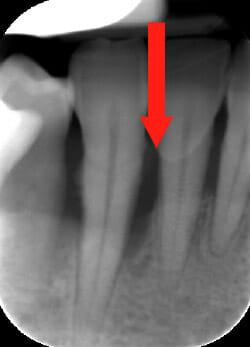

Endorale prima e dopo la cura della parodontite

Con terapia parodontale fotodinamica non chirurgica: si noti la ricrescita naturale dell’osso e del tessuto parodontale.